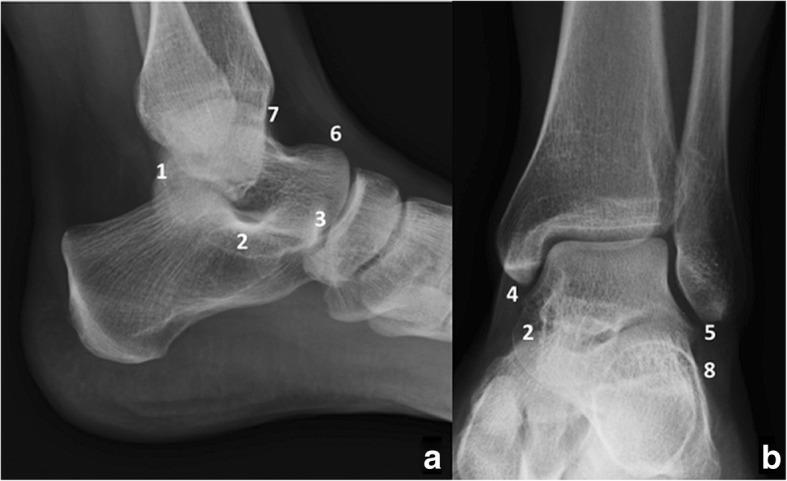

Accessory anatomical structures in the ankle and foot usually represent incidental imaging findings; however, they may also eventually represent a source of pathology, such as painful syndromes, degenerative changes, be the subject of overuse and trauma or appear as masses and cause compression syndromes or impingement.This review aims to describe and illustrate the imaging findings related to the presence of accessory ossicles and muscles in the ankle and hindfoot through different techniques, with special attention to those variants that associate factors of clinical relevance or that trigger challenges in the differential diagnosis.

踝关节和足部的附属解剖结构通常为偶然的影像学表现;然而,它们最终也可能成为病理来源,如疼痛综合征、退行性改变、过度使用和创伤的对象,或表现为肿块并导致压迫综合征或撞击。本综述旨在通过不同技术描述和展示与踝关节和后足附属小骨和肌肉存在相关的影像学表现,特别关注那些与临床相关因素相关或在鉴别诊断中引发挑战的变异。